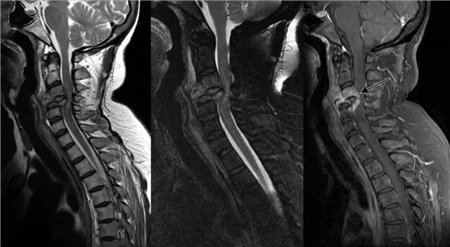

人体正常的颈椎是有弧度的,大约是前凸30°-45°。但是随着颈椎长时间承受巨大压力,过于疲劳的状态。于是,弧度就逐渐退化变直,甚至反弓。

前凸的颈椎曲度被改变,结果就是引发颈椎间盘突出,造成对血管和神经的压迫,容易出现颈椎僵硬、头晕、头痛的症状。

颈椎病是由于颈椎间盘退行性变、颈椎骨质增生所致颈椎管或椎间孔变形、狭窄,刺激、压迫颈部脊髓、神经根、交感神经及软组织造成其结构或功能性损害所引起的一系列临床症状的综合征。颈椎病可分为颈型、神经根型、脊髓型、椎动脉型、交感神经型和其他型。颈椎病临床常表现为颈、肩臂、肩胛上背及胸前区疼痛,臂手麻木,肌肉萎缩,甚至四肢瘫痪,以及神经压迫导致的失眠、头痛、头晕等。可发生于任何年龄,以40岁以上的中老年人为多。颈椎病具有发病率高,治疗时间长,治疗后极易复发等特点。